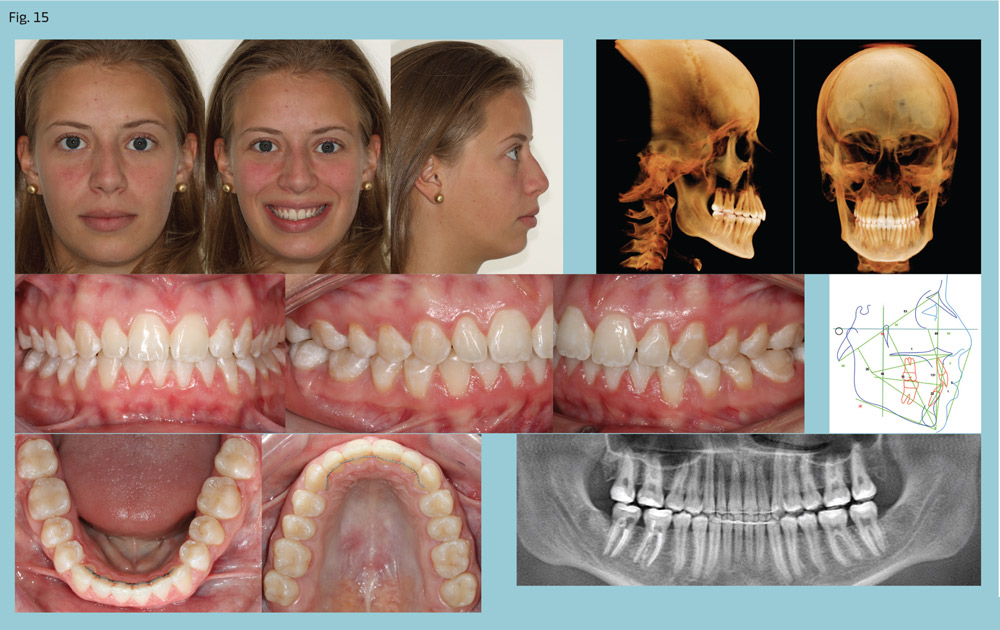

After four months of leveling and alignment, PowerScope was placed (Figs. 12-13). The Class II was corrected in three months (Fig. 14) and PowerScope removed. After another three months for coordinating the arches and detailing the occlusion, fixed appliances were debonded, completing 10 months of active treatment (Fig. 15).